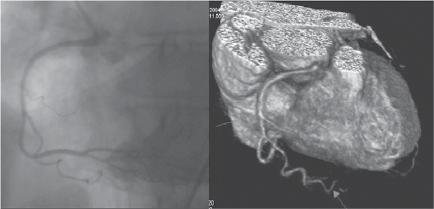

From an ECG standpoint, coronary angiography (Figure 1.1) is especially important in the acute phase for diagnosing the disease and correlating the site of occlusion with the ST‐segment deviations. It is also useful in the chronic phase of the disease. However, in the chronic phase of Q‐wave myocardial infarction (MI) the ECG does not usually predict the state of the coronary tree, because revascularization has often modified the characteristics of the occlusion responsible for the MI (Basso and Thiene 2006). Moreover, coronary angiography is insensitive for detecting minor collaterals that could attenuate ischemia. Coronary angiography does not give information about the myocardium and, thus, cannot directly assess the extent and severity of ischemia, especially in the acute phase of acute coronary syndromes (ACSs).

Figure 1.1 (A) Normal case: coronary angiography (left) and three‐dimensional CTA (right) showing normal left anterior descending (LAD, arrow) and left circumflex (LCX) coronary arteries. The latter is partially covered by the left appendix in CTA. (B) Normal case: coronary angiography (left) and CTA (right) showing a normal dominant right coronary artery (RCA). (C) An 85‐year‐old man with atypical chest pain: (a) Maximal intensity projection (MIP) of CTA with tight mid‐LAD stenosis that correlates perfectly with coronary angiography (b). (D) Similar case as (C) but with the stenosis in the proximal RCA. (a–d) CTA and (e) coronary angiography. (E) A patient with tight stenosis in the LCX before a bifurcation. (a) and (b) CTA and (c) coronary angiography. (F) These images show that CTA may also demonstrate the presence of stenosis in distal vessel branches, in this case in the posterior descending branch of the RCA. (a–b) CTA and (c) coronary angiography. (G) These images show that CTA (a, b) may delineate the length of a total occlusion and visualize the distal branches (see arrows in (b)). Collateral flow from the LAD to the RCA may be better visualized with CTA than with conventional coronary angiography (c: here only the RCA is shown). (H) A 42‐year‐old patient with a stent implanted in the LAD six months before. The patient complained of atypical chest pain and underwent CTA. The MIP images of CTA (a–c) show no significant restenosis, but some plaque formation in the left main trunk (d, circle) that was not well seen in coronary angiography (e). The degree of luminal obstruction by the plaque can be exactly measured by intravascular ultrasound (IVUS) (f). The ECG showed mildly inverted T waves in V1–V3 during follow‐up (see Plate 1 in color plates).

The myocardium and conduction system (CS) are perfused by the right coronary artery (RCA), the left anterior descending coronary artery (LAD) and the left circumflex coronary artery (LCX). Figure 1.1 shows the typical correlation of coronary angiography and CTA in the normal coronary tree and in some anatomic variants.